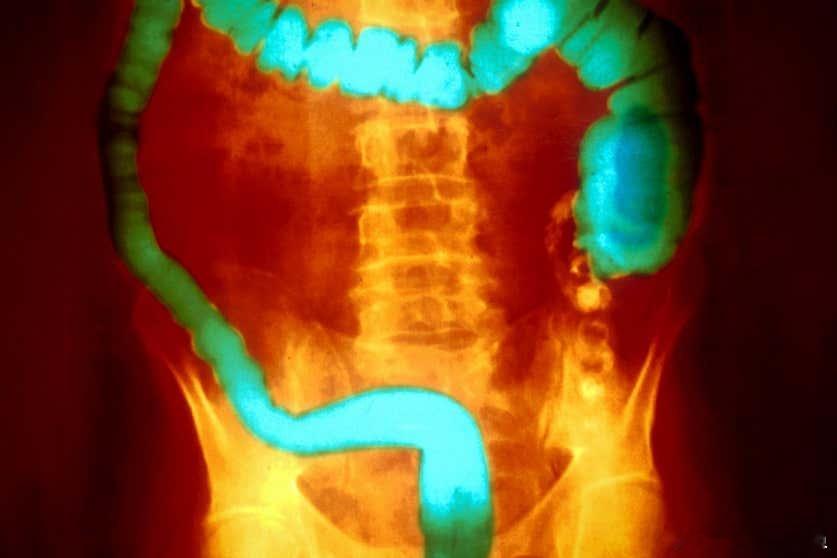

新研究发现:溃疡性结肠炎与脏水的毒素有关!11月20日,发表在Newscientist上的一项最新研究揭示,脏水中常见的细菌所产生的毒素可能是引发溃疡性结肠炎的关键因素。这一发现不仅为该疾病提供了新的病因解释,更为开发全新治疗方法开辟了道路。溃疡性结肠炎作为炎症性肠病的主要类型之一,其特征为结肠和直肠内壁的慢性炎症,患者常经历无症状期与发作期交替的病程,严重者甚至需切除结肠。尽管医学界普遍认为该病与自身免疫机制及遗传、环境因素相关,但其确切病因始终未明。研究人员经过一系列人体与动物实验发现,存在于脏水中的气单胞菌属细菌能够产生一种名为“气单胞菌溶素”的毒素。这种毒素具有高度选择性,能精准杀死结肠内壁的巨噬细胞——这是一类在调节局部免疫反应中扮演关键角色的免疫细胞。进一步的机制研究发现,气单胞菌溶素对巨噬细胞具有极强的破坏力,而对其他肠道细胞影响甚微。当研究人员用能产生这种毒素的细菌感染小鼠时,小鼠的结肠炎易感性显著增加;然而,通过基因编辑技术删除细菌的毒素基因,或使用抗体中和毒素,都能有效预防结肠炎的发生。流行病学数据同样支持这一发现,在79名溃疡性结肠炎患者中,72%携带气单胞菌;而在480名健康对照者中,这一比例仅为12%。这一突破性认识为开发针对特定细菌毒素的精准疗法提供了全新方向,有望为溃疡性结肠炎患者带来更有效的治疗选择。